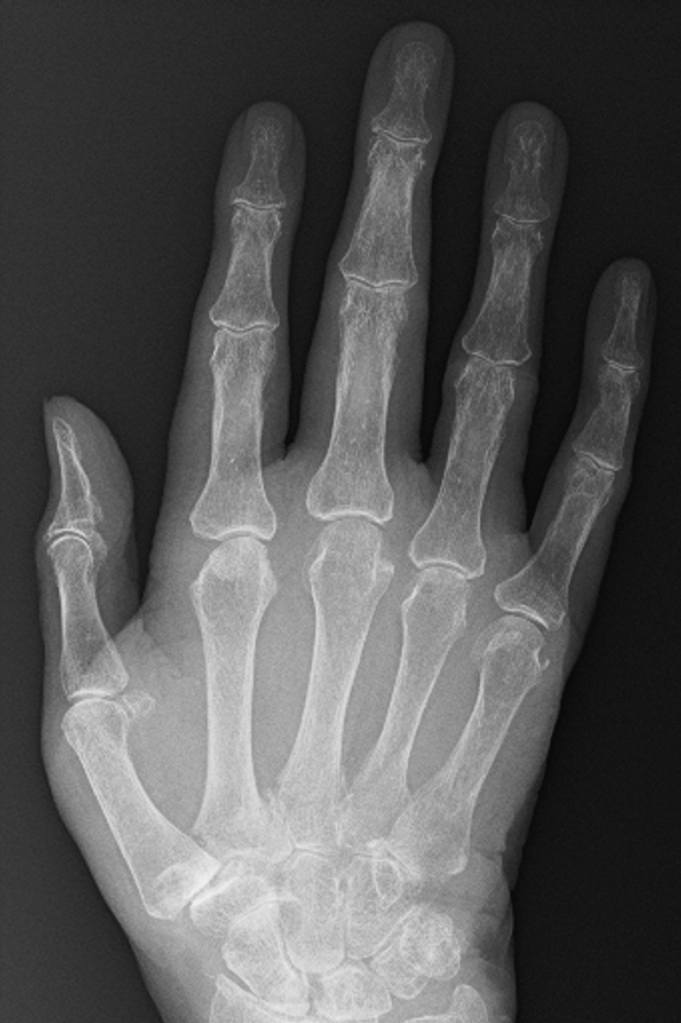

How do we know whether there is arthritis in a joint from an X-ray?

Osteoarthritis has a very characteristic appearance on X-rays, making it relatively easy to exclude any other types of arthritis.

There are four features of osteoarthritis on an X-ray:

– Loss of joint space

– Sub-chondral sclerosis

– Osteophyte formation

– Cyst formation

Loss of joint Space

In young patients, there are thick cartilage caps on the ends of the bones within the small joints of the hand. With age, these cartilage caps slowly wear from constant use, despite the body’s regenerative processes. A normal joint, therefore, has much less cartilage at 50 than at 20, and by the time people reach 80+ years, there is often very little cartilage left.

The GAP between the bones on an X-ray represents the space occupied by the cartilage, and it is very easy to predict how much cartilage is left in a joint simply by looking at the amount of space between the bones – the more space the more cartilage, and generally speaking the more healthy the joint.

Subchondral Sclerosis

Subchondral simply means ‘under the cartilage‘, and sclerosis is the name given when bone appears thicker or whiter on an X-ray. When cartilage is lost from the joint, bone articulating with bone triggers a process where the body tries to increase the density of the remaining bone to protect it – on an X-ray, this gives an appearance of whiteness around the joint, because less X-rays can pass through this thickened bone and make it to the X-ray plate.

Osteophyte Formation

The stability of a joint depends on the shape and fit of the bone on either side of the joint, and the soft tissues around the joint. In particular, the small joints of the hands have collateral ligaments on either side of the joint, and a tough sheet of fibrous cartilage (volar plate) on the palm side of the joint. These soft tissue structures prevent abnormal movement in the joint.

Where the joint surfaces have worn away, the ligaments and volar plate become slightly too long for the remaining gap, allowing movement of the joint in an abnormal way. The body responds by laying extra bone around the joint in order to make it stable. The extra bone is called an osteophyte, and this usually makes the joint stiffen up considerably.

Cyst Formation

Cysts represent areas where the bone has been resorbed or dissolved away by the body. They occur around the arthritic joint, and are thought to occur in response to increased pressure around the arthritic joint. This, in turn, can interfere with the normal blood flow and facilitate cyst formation.